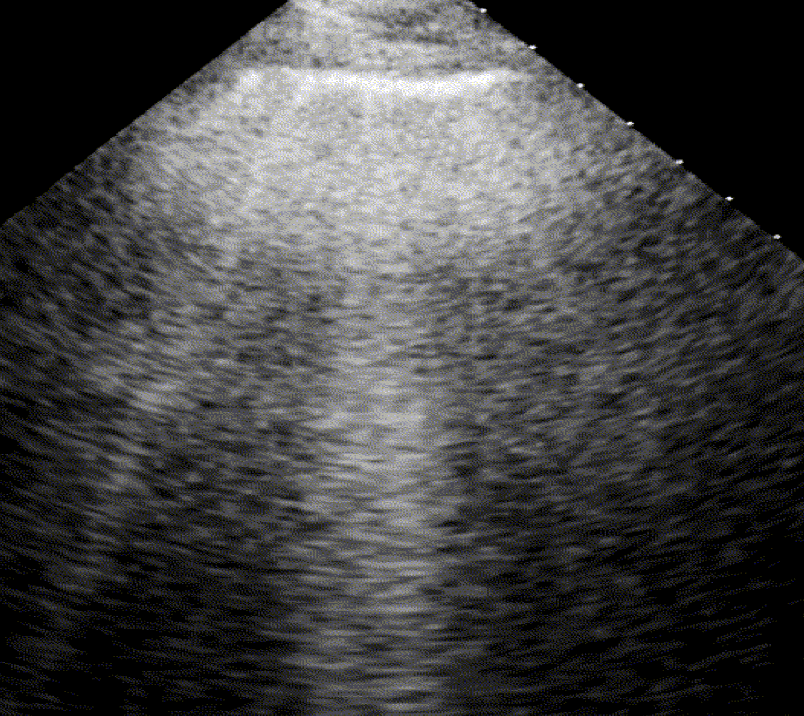

B-lines

For the cardiologist, the primary application of lung ultrasound is the assessment of B-lines. These vertical, laser-like reverberation artifacts arise from the pleural line and extend to the bottom of the screen without fading. B-lines move synchronously with respiration (lung sliding), erase underlying A-lines, and share the same echogenic intensity as the pleural line.

When fluid or inflammatory exudate accumulates in the lung interstitium, ultrasound waves reverberate between air–fluid interfaces, generating B-line artifacts. The presence of more than two B-lines per intercostal space indicates that the lung tissue is no longer fully air-filled. While few isolated B-lines may be seen in healthy lungs (lung fissures may cause few B-lines), the appearance of three or more B-lines within a single intercostal space is considered pathological.

Pathophysiological Progression

Lung ultrasound provides direct insight into interstitial fluid accumulation. Before alveolar flooding occurs, fluid fills and thickens the interlobular septa of the interstitium. At this early stage—when alveoli are still air-filled—the sonographic pattern transitions from an A-profile (air-dominant) to a B-profile (fluid-dominant).

Notably, B-lines appear on ultrasound much earlier than Kerley B-lines on a chest radiograph and often precede clinical symptoms.

B-lines correlate with the thickening of subpleural interlobular septa in pulmonary interstitial edema.

Confluent B-lines

Cardiogenic Pulmonary Edema

In cardiogenic pulmonary edema, the presence of three or more B-lines per intercostal space together with preserved lung sliding on both sides is characteristic. As edema worsens and air content decreases, B-lines increase in number, become broader and confluent, and may fill the entire lung field, producing an appearance of an almost uniformly bright (“white”) lung. The number and density of B-lines correlate closely with the severity of pulmonary congestion.